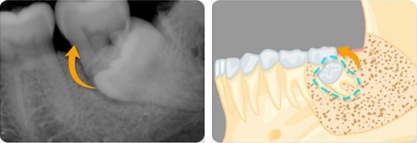

매복치로 인해 영구치 뿌리가 흡수되었을 경우

같은편의 제2대구치는 건강하나 제1대구치의 손상이 심한 경우